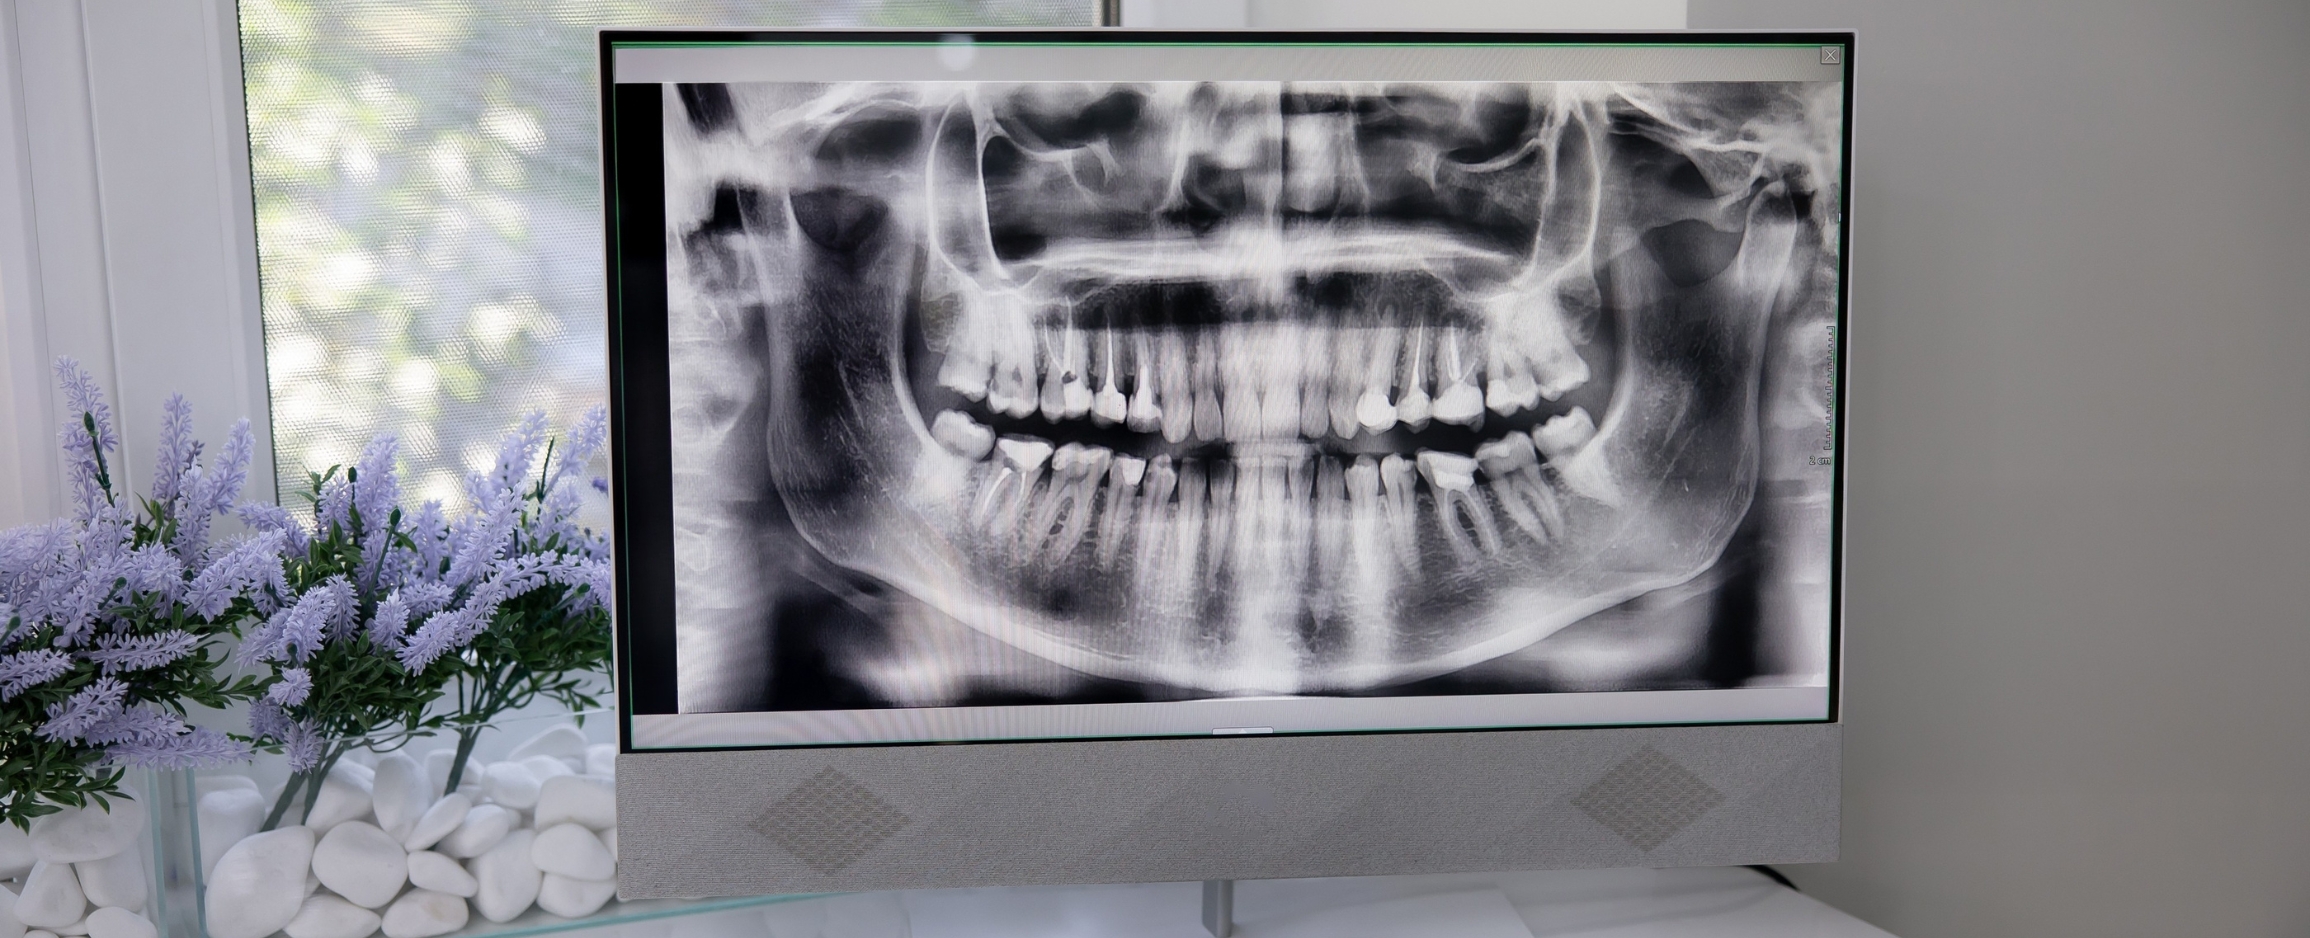

2D panoramic radiography

This examination produces a 2D image of all your teeth and jaws (including buried teeth), and is useful for planning dental treatment, orthodontics, oral surgery, or simple dental implant surgery.